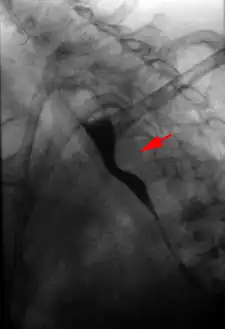

Aberrant right subclavian artery at angiography.